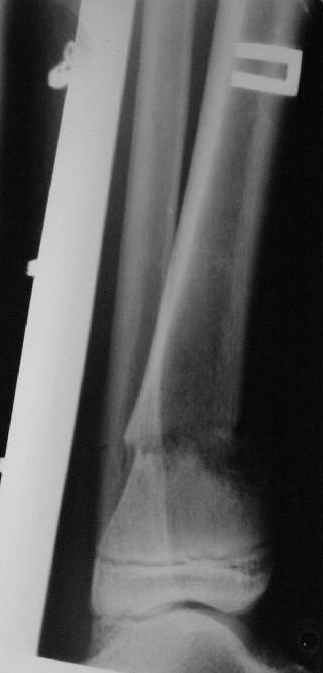

Так как речь зашла непосредственно о травме, см этапные

снимки. Как все было

Первичные

Вытяжение

Фиксация

в гипсе

Промежуточный